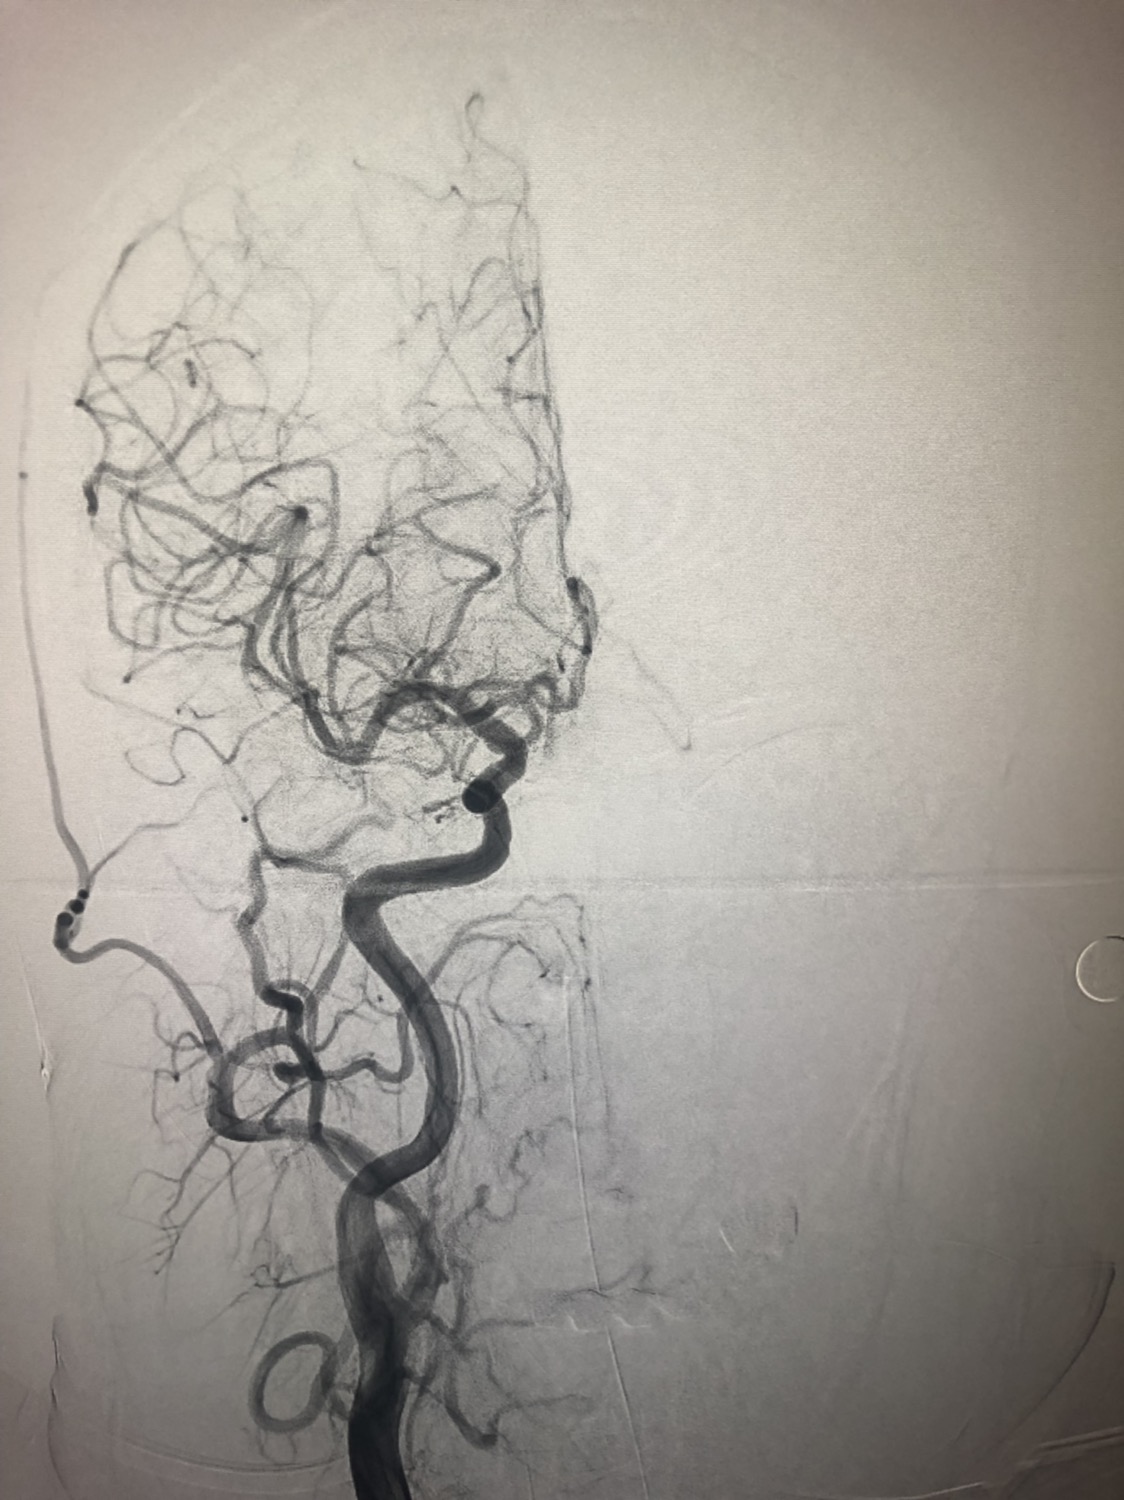

急诊二。zde,f53y。

意识模糊进行性加重8h,基底动脉闭塞,reco取栓再通,貌似动脉硬化,实际血管光滑。造影➕取栓8min。今日团队配合紧密,不到三小时全麻造影取栓带苏醒完成两台取栓。团队棒棒的!南阳市中心医院神经内科脑血管病介入团队